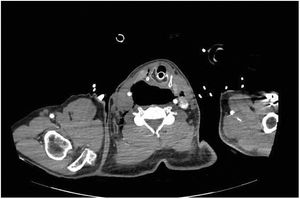

A 61-year-old man with a history of achalasia treated in 2015 with fundoplication, without other known conditions, presents to the ER with sudden dyspnea and acute hypoxemic respiratory failure. On physical examination, leftward tracheal deviation with cervical edema and subcutaneous tissue crepitus is observed (Fig. 1). Once stabilized with endotracheal intubation and connected to invasive mechanical ventilation, suspicion of esophageal disease leads to a contrast-enhanced thoracic CT scan that confirms the presence of a 7 cm megaesophagus (AP axis) with fluid and air levels inside (Fig. 2), and bubbles of pneumomediastinum with extensive cervical subcutaneous emphysema (Fig. 3), which are consistent with cervical esophageal perforation. Definitive treatment: esophagectomy.